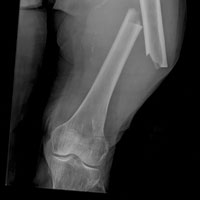

Согласно данным Центров по контролю и профилактике заболеваний (Centers for Disease Control and Prevention), США, около 250 тыс. американцев в возрасте ≥65 лет подлежат госпитализации из-за перелома бедренной кости, причиной большинства из них является падение. Специалисты Больницы Генри Форда (Henry Ford Hospital), США, выявили связь между гипотермией во время операции по поводу перелома бедренной кости и повышенным риском развития инфекционных осложнений у пациентов пожилого возраста с низким индексом массы тела. Результаты исследования представлены в форме доклада на Ежегодном собрании Американской академии хирургов-ортопедов (American Academy of Orthopedic Surgeons).

В своей работе они проанализировали данные 1525 пациентов, перенесших оперативное вмешательство по поводу перелома бедренной кости в период января 2005–октября 2013 г. В исследовании специалисты изучали влияние гипотермии во время операции на частоту развития инфекционных осложнений у пациентов ортопедического профиля. Гипотермией считалось снижение температуры тела ниже 36 °С (96,8 °F). К основным причинам развития гипотермии во время операции относились чрезмерное оголение участков кожи, введение препаратов для анестезии, а также других лекарственных средств в форме раствора и др.